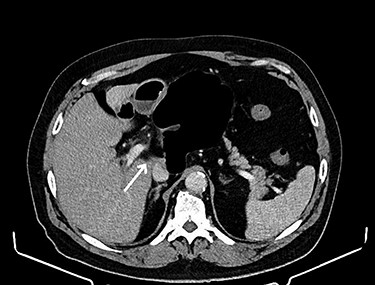

CT of the abdomen is considered the gold standard of the diagnosis of the internal hernia through the foramen of Winslow. The most prominent feature is the presence of intestinal loops between the inferior vena cava and portal vein [4] (see Fig. 1). Another classic feature is the presence of distended intestinal loops posterior to the stomach, which is displaced along with first and second part of the duodenum to the left [5] (see Fig. 2).

Intestinal loops (arrow) between the inferior vena cava and portal vein.